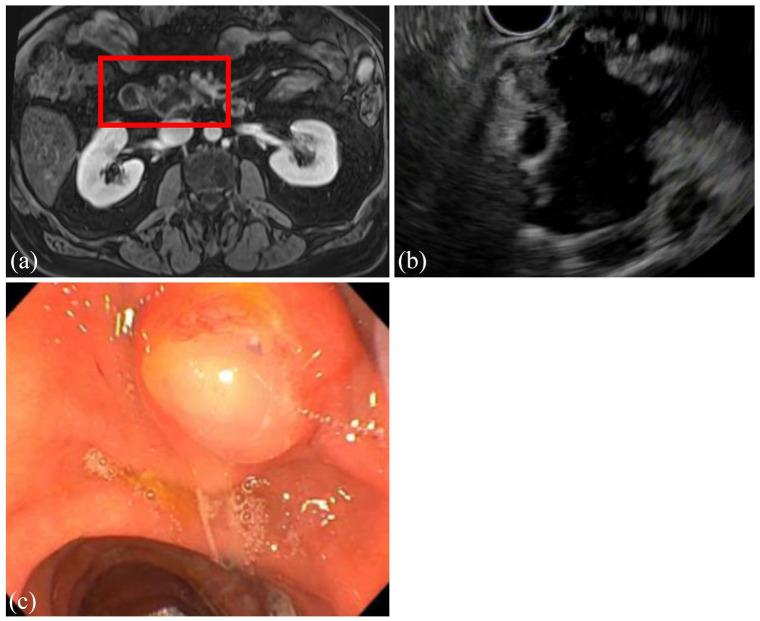

在过去十年中,胰腺囊肿的患病率显著上升,部分原因是横断面成像的质量和频率提高。虽然大多数囊肿不会发展为癌症,但少数会发展,需要进行随访。由于多种指南的建议各不相同,胰腺囊肿的管理可能既令人困惑又令人生畏。尽管指南的具体内容存在差异,但它们都认同几个高风险特征,在评估胰腺囊肿时,任何临床医生都应关注这些特征:存在壁结节或实性成分、主胰管扩张(或存在主胰管内乳头状黏液性肿瘤)、胰腺囊肿大小≥3 - 4厘米,或胰腺囊肿液抽吸细胞学检查呈阳性。其他需要考虑的重要标准包括囊肿快速生长(≥5毫米/年)、血清糖类抗原19 - 9水平升高、新发糖尿病或被认为与囊性病变相关的急性胰腺炎。